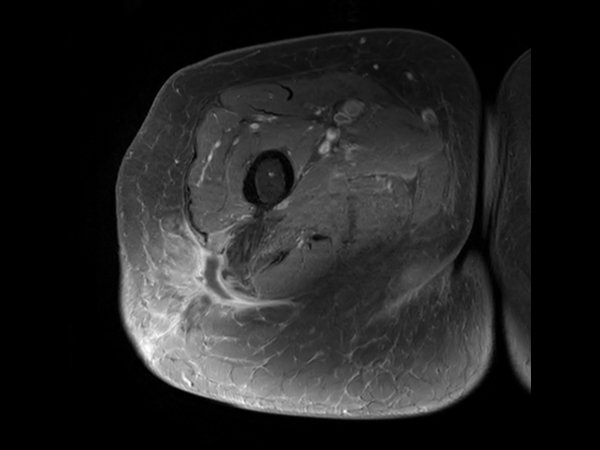

Axial T2w mDIXON XD TSE (Water only)